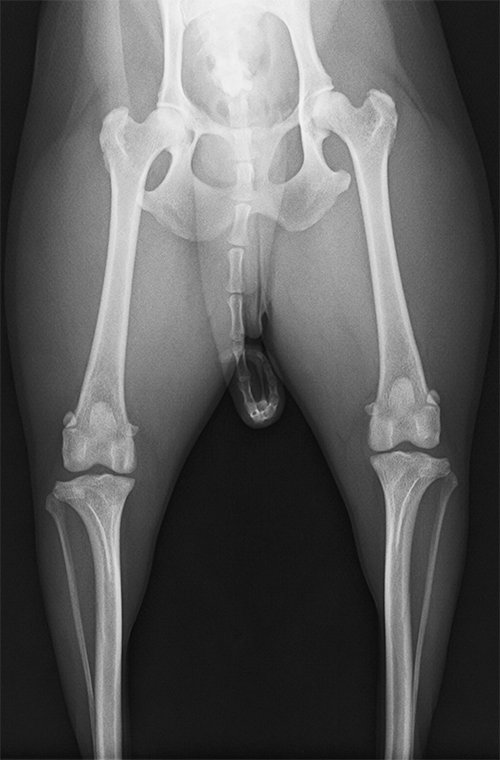

正常な膝蓋骨

膝関節部分は上下(大腿骨と脛骨)がきちんと揃っており、隙間もなくはまっているのがわかる。膝蓋骨は大腿骨下部の丸い影の部分。全体的に一直線になっている点も重要。

内包脱臼を起こした膝蓋骨

右の正常な膝蓋骨の写真に比べると大腿骨が幾分内側に寄っているのがわかる。大腿骨下部中央にあるはずの膝蓋骨はかなり内側に寄っている。そのため外れやすくなる。